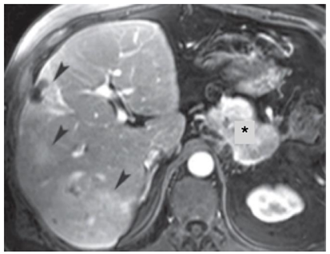

Observe a imagem a seguir:

Na imagem acima de RM ponderada em T1 com supressão de gordura pós-contraste, as estruturas indicadas pelo asterisco e pelas cabeças de setas identificam, respectivamente,